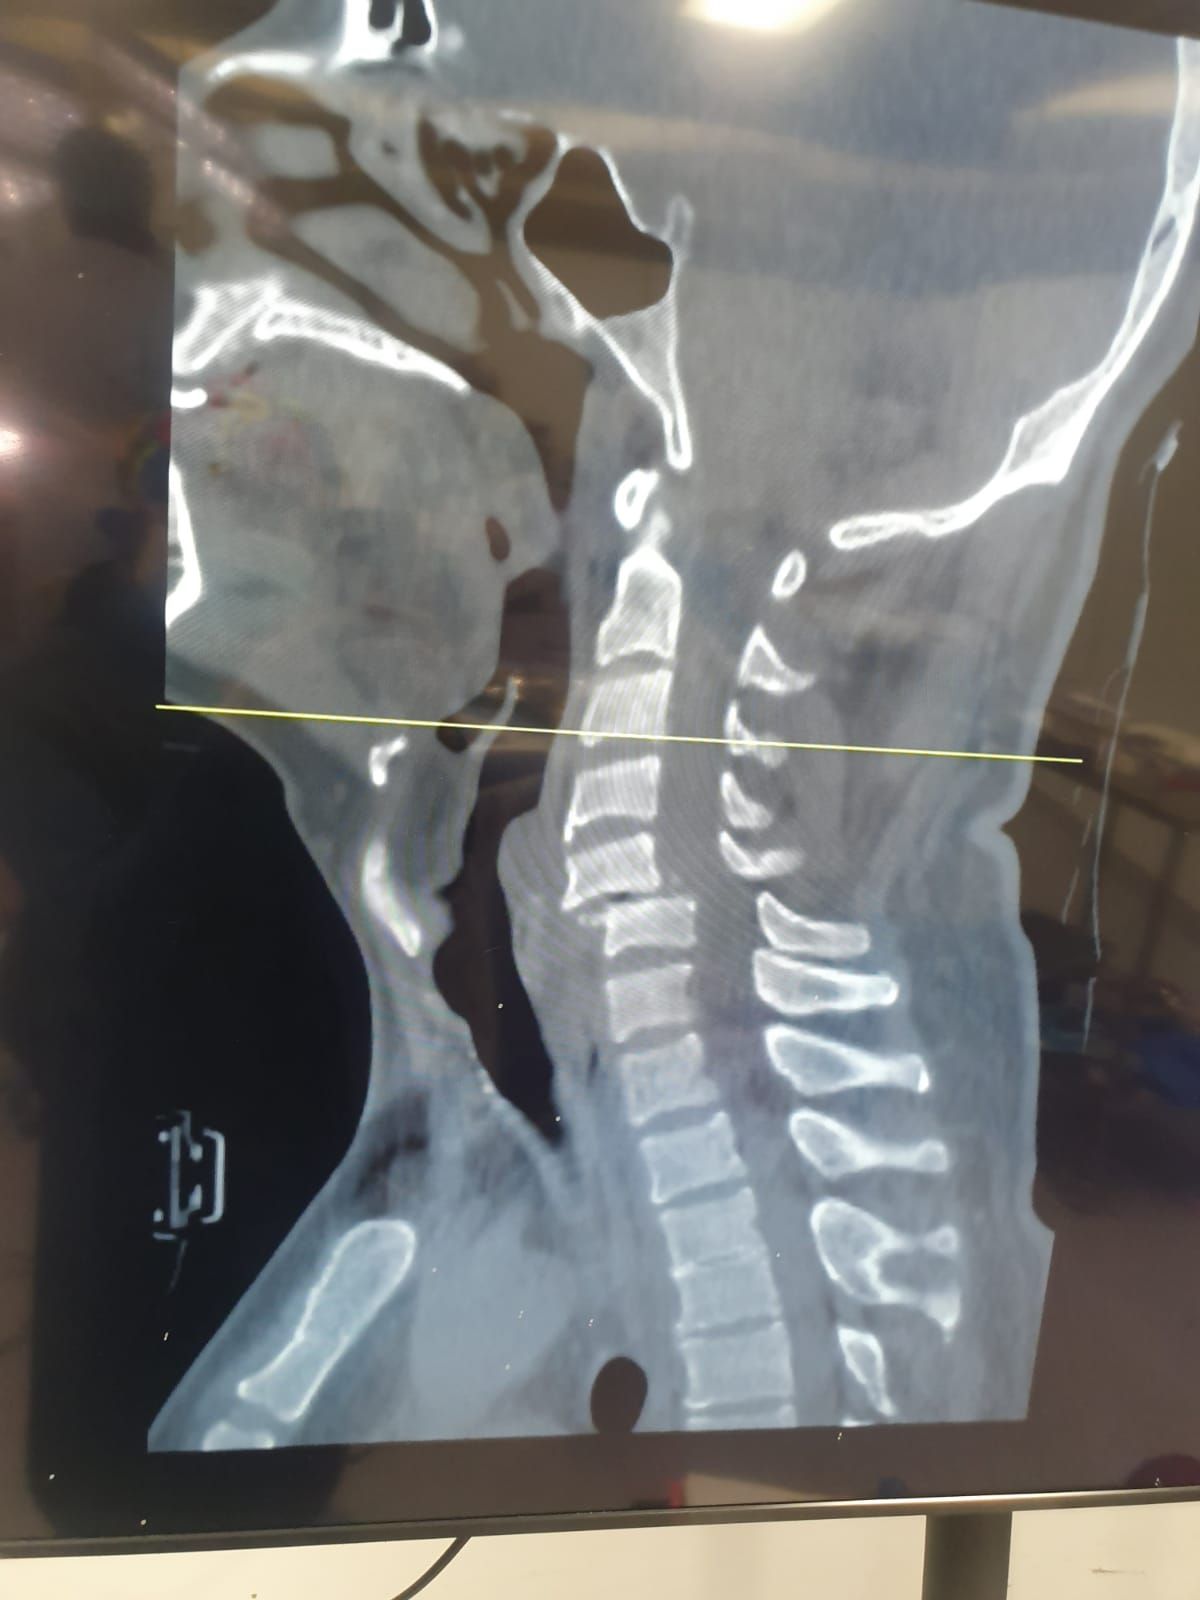

- Cirugía de Columna

- Alta Especialidad en Cirugía de Columna - Universidad La Salle

- Hernia de disco

- Inflamación de columna

Sin especificarArtrodesis cervical anterior